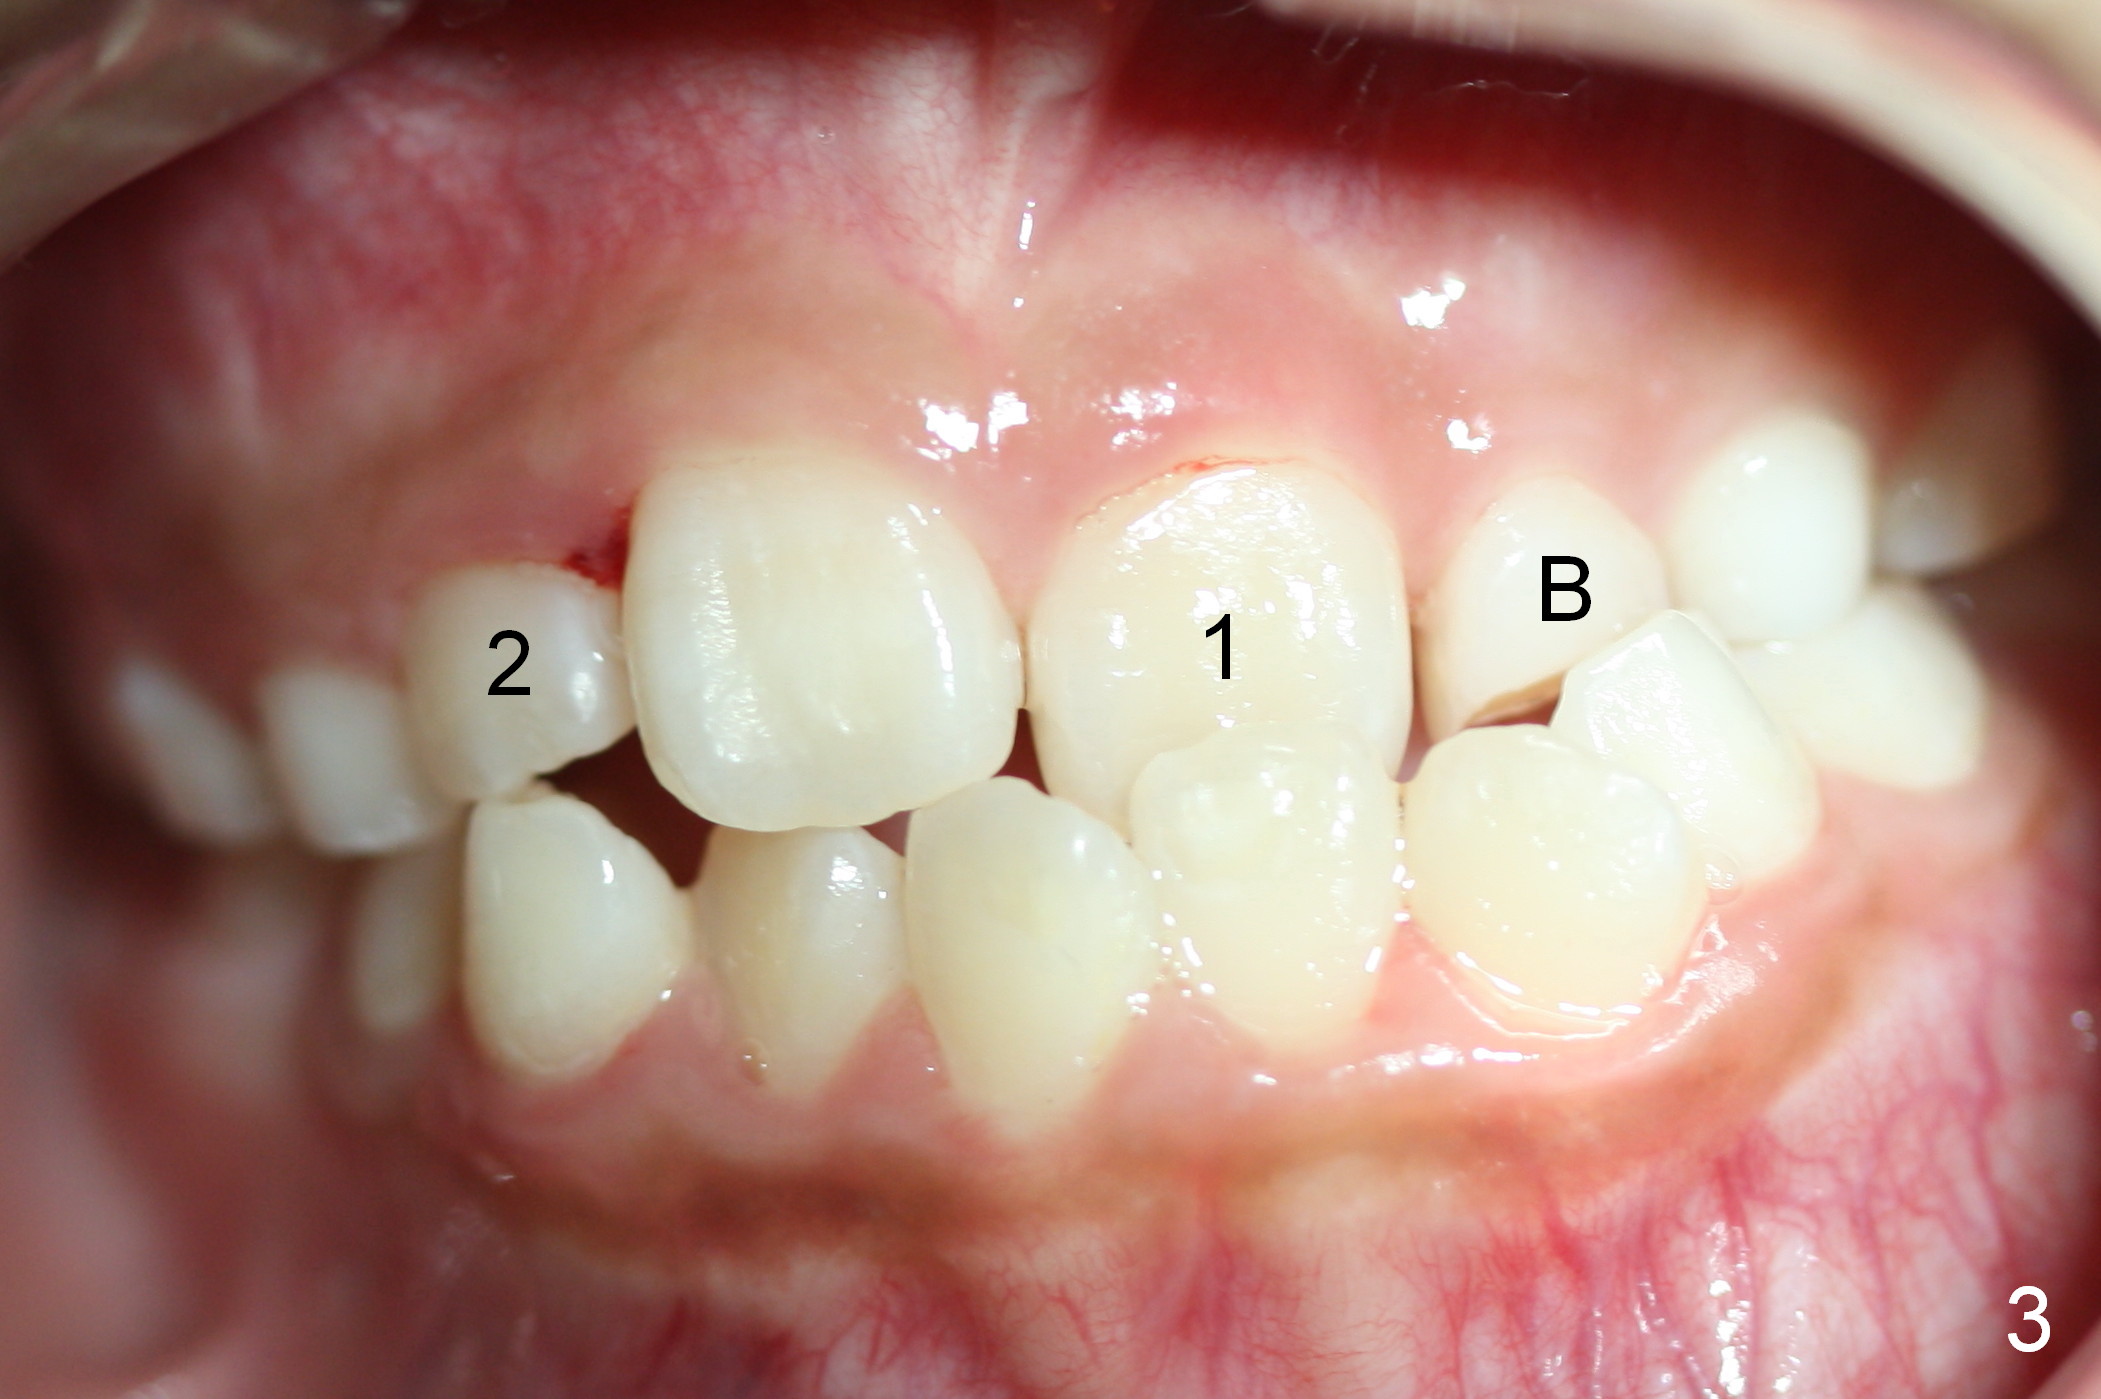

A 9-year-old girl has maxillary retrusion (Fig.1,2). Intraorally, it is manifested as the upper left anterior cross bite and underdevelopment (Fig.3: 1, B). B has mobility. UL6 is incompletely erupted. The 1st stage consists of B extraction, upper (U) bracketing, all 6s' banding, retraction between UL and LL 6s (to facilitate UL 6 eruption) and adding composite to U Es.